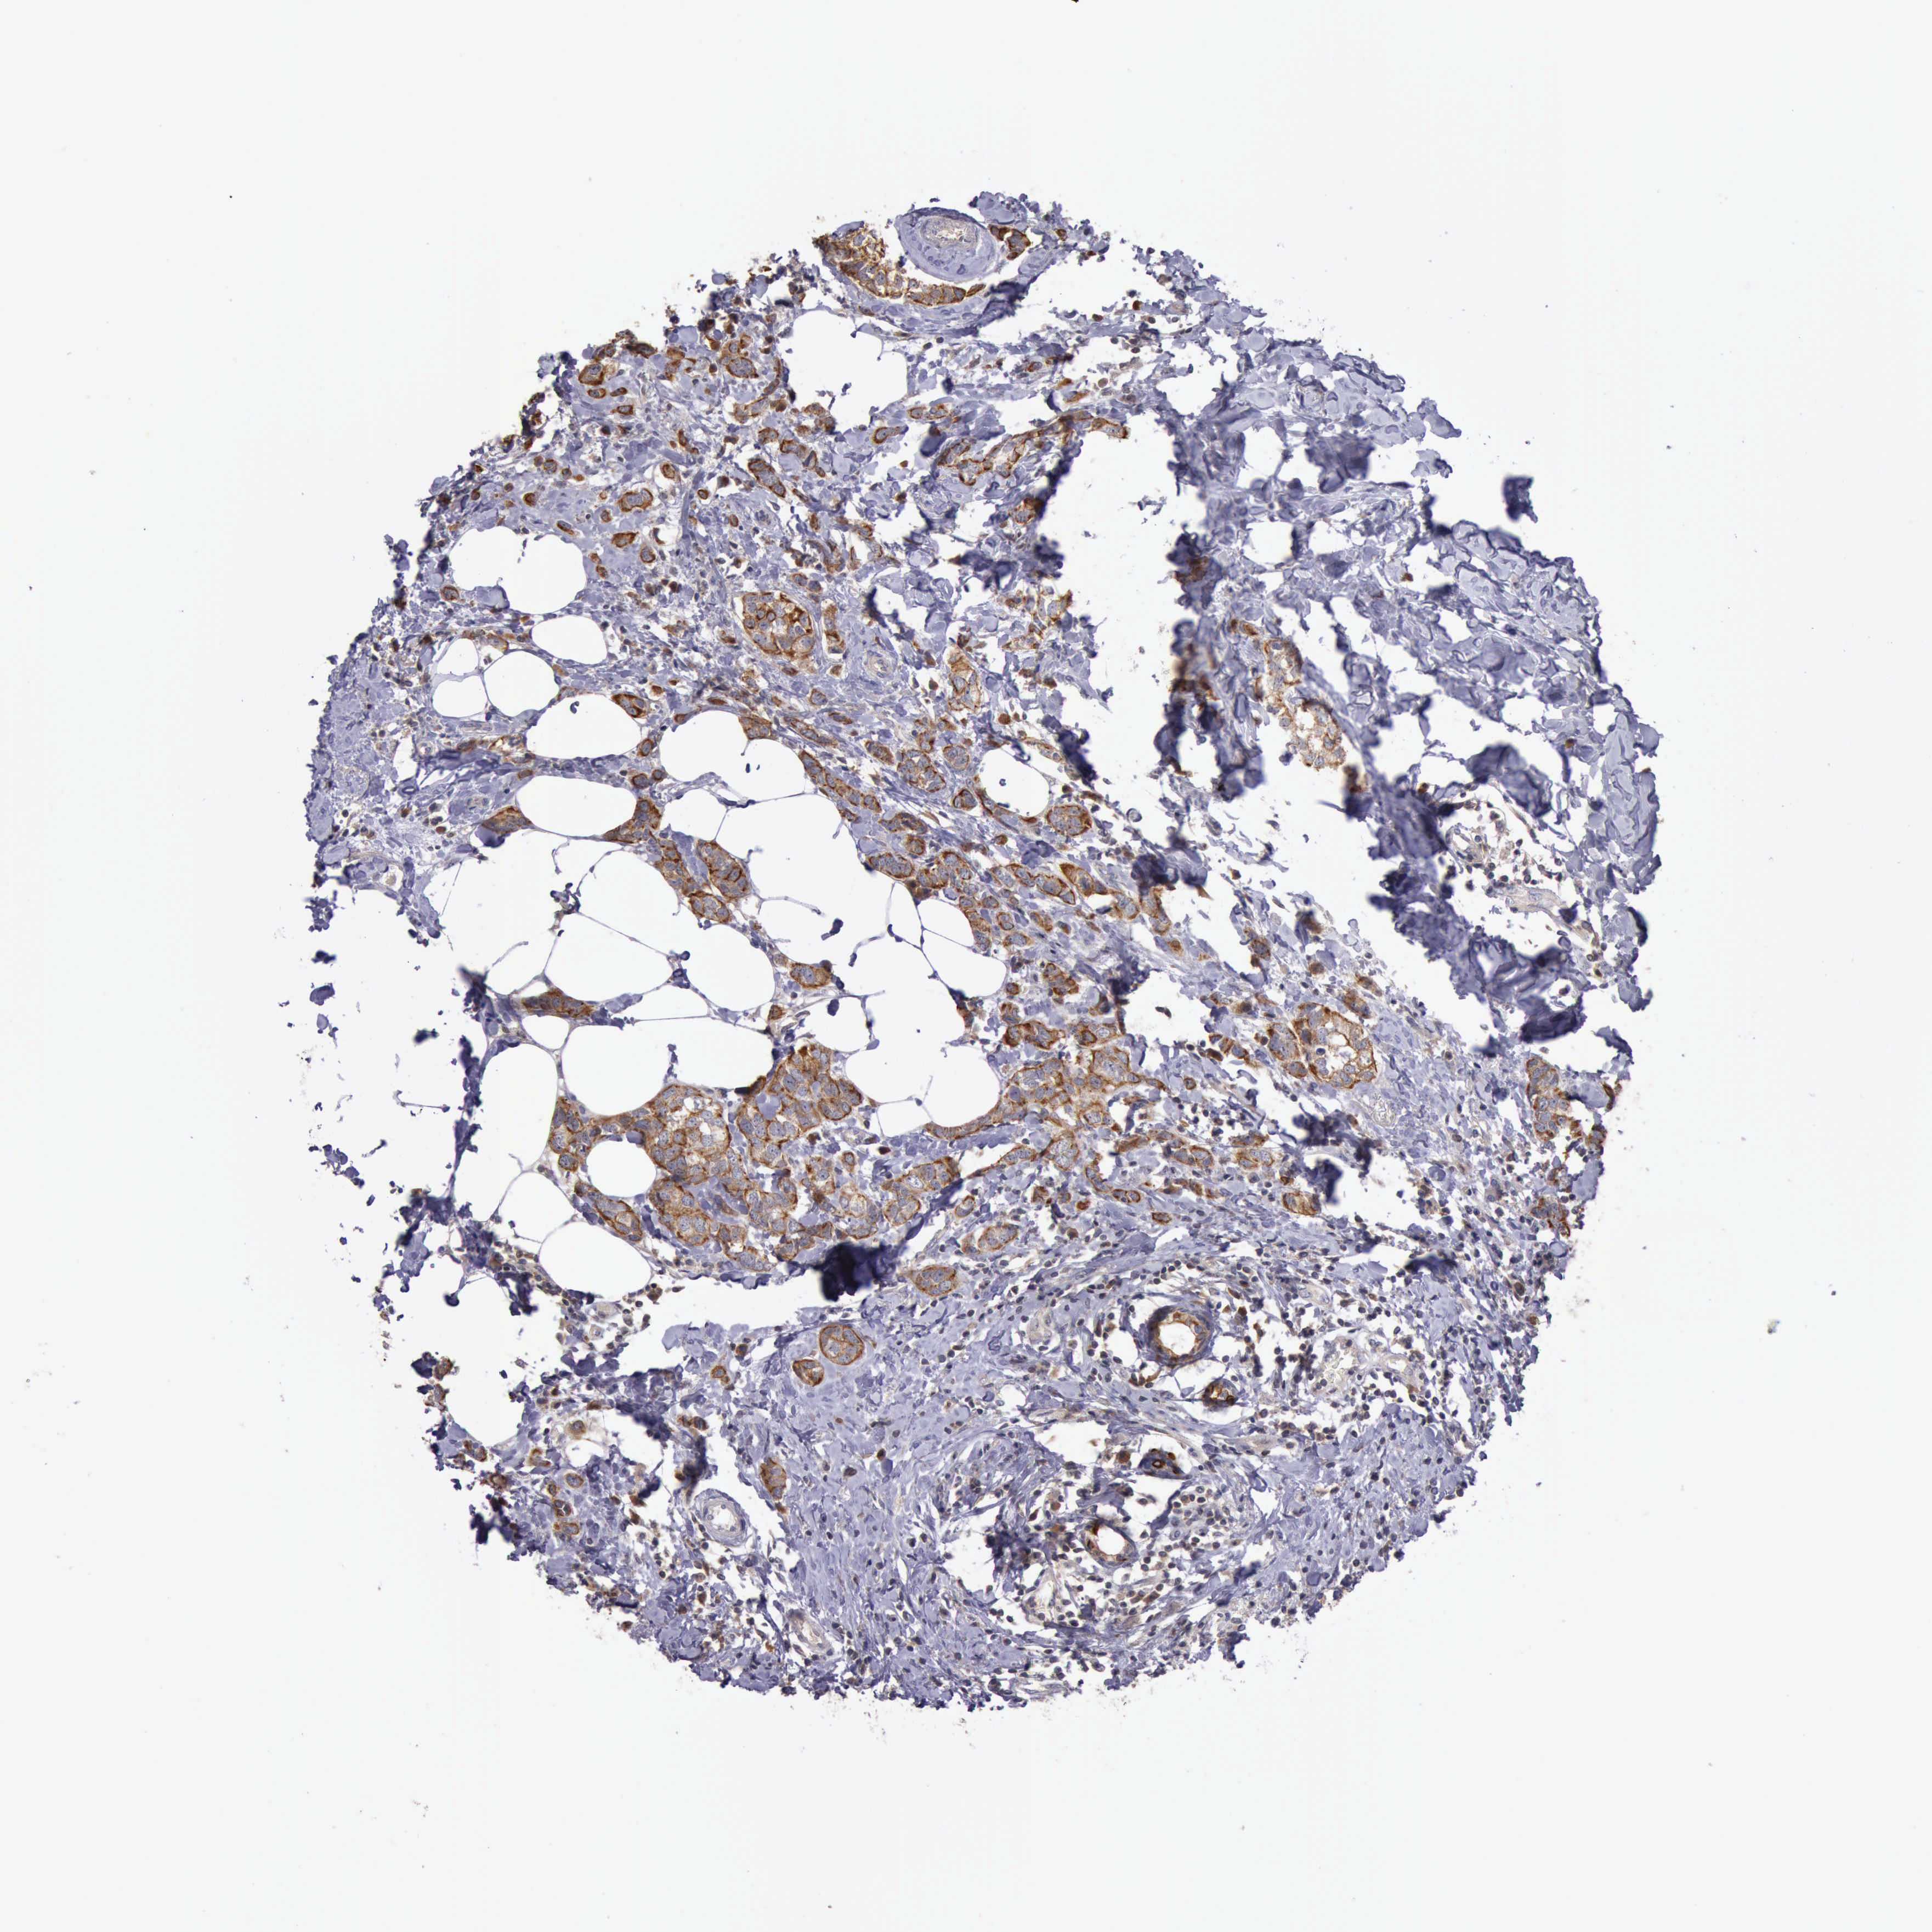

CANCER BREAST CANCER Show tissue menu

BRCA TCGA BRCA VALIDATION PROTEIN EXPRESSION

ANTIBODIES

AND

VALIDATION